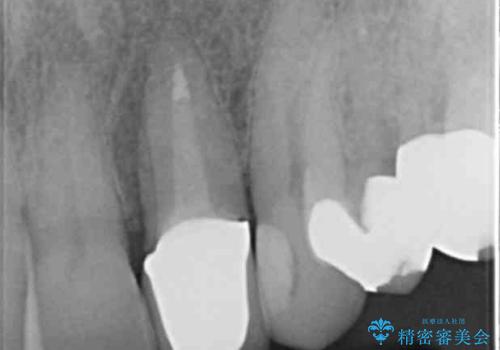

根管治療が為されたまま、クラウンの装着が行われず変色し審美障害を来している状態です。

維持を保つためのファイバーコア築盛を行い、精密なジルコニアクラウン製作を行います。